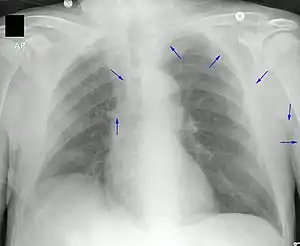

A PICC is inserted in a peripheral vein such as the cephalic vein, basilic vein or brachial vein in the arm, and then threaded through the veins toward the heart, until the end of the catheter rests in the distal superior vena cava or cavoatrial junction. They must be inserted by a trained medical professional, including a physician, but also any trained medical professional such as a specially trained registered nurse.[5] An ultrasound or chest X-ray, or the use of fluoroscopy, can be used during insertion and to confirm placement. The insertion is a sterile procedure, but does not need to be performed in a completely sterile environment like an operating room.